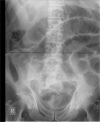

Acute appendicitis is a common surgical problem however the diagnosis is often overlooked when it presents as a small bowel obstruction. In this report we present two cases of elderly patients who presented with small bowel obstruction and raised inflammatory markers. Both patients were successfully treated with a laparotomy, adhesiolysis and appendicectomy and went on to make a good recovery.